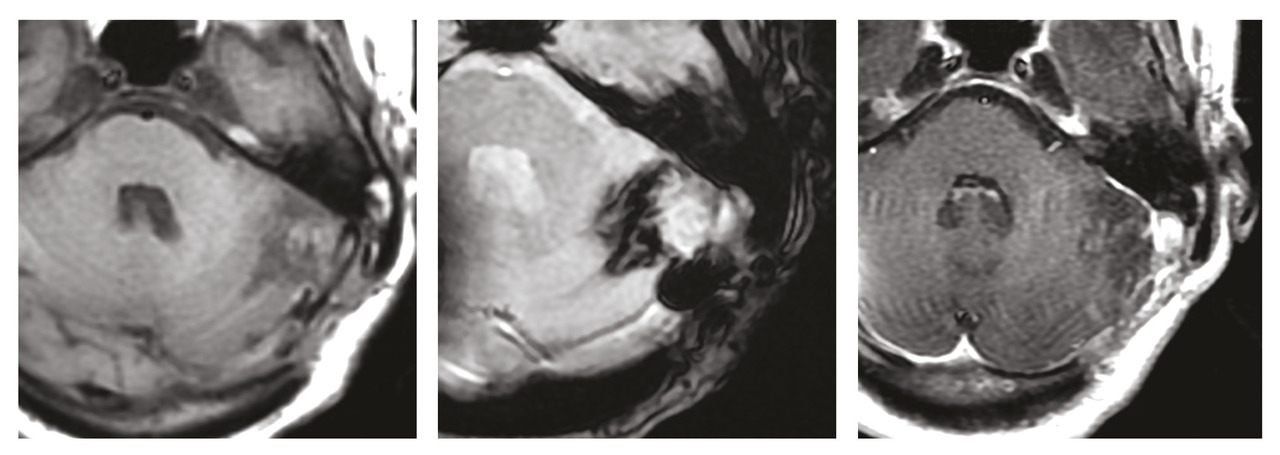

Une IRM de contrôle réalisée deux mois après le geste opératoire montre des stigmates hémorragiques sans résidu tumoral.